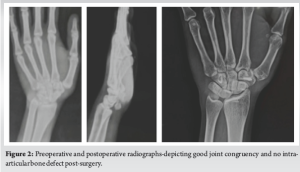

A 20-year-old female patient presented with non-traumatic popping of the metacarpophalangeal (MCP) joint for the past 3 years. She reported being unable to perform strenuous activities due to this condition. There was no history of trauma, negative family history, no signs of ligament laxity; on the other hand, it was normal. Clinically, the patient’s MCP joint demonstrated popping without any external force (Fig. 1). On examination, there were no visible deformities, swelling, or signs of ligament laxity. The ROM was normal in both hands except for the affected MCP joints. Standard radiographs of the hand and MCP joint were taken, which did not reveal any fractures or dislocations (Fig. 2).

The approach used an anterior curvilinear incision along the CMC joint’s lateral margin from the distal wrist crease up to the FCR tendon. Radial nerve branches, the cutaneous palmar branch of the median nerve, and superficial branches of the radial artery were protected. CMC joint exposure was done by reflecting the thenar muscles extra-periosteally, and the articular surface cartilage was visualized for damage and was found to be healthy and intact. Equidistant mini-incisions were made in the forearm proximally, and the FCR tendon was harvested with artery forceps by gradual retraction along subsequent incisions. FCR tendon hooked along the trapezius and routed through extra-articular bone tunnel along dorsum of the thumb metacarpal parallel to articular surface and along direction of anterior oblique ligament for the purported action FCR tendon sutured covering dorsoradial and volar beak ligament under adequate tensile force (Fig. 3). For additional stability and robust support a single loaded 2.7 mm suture anchor used for capsule stabilization and resuturing, wound closed in layers with protective thumb splint given over 6 weeks, followed by gradual physiotherapy of hand and regular follow-ups at 3 month intervals (Fig. 4).